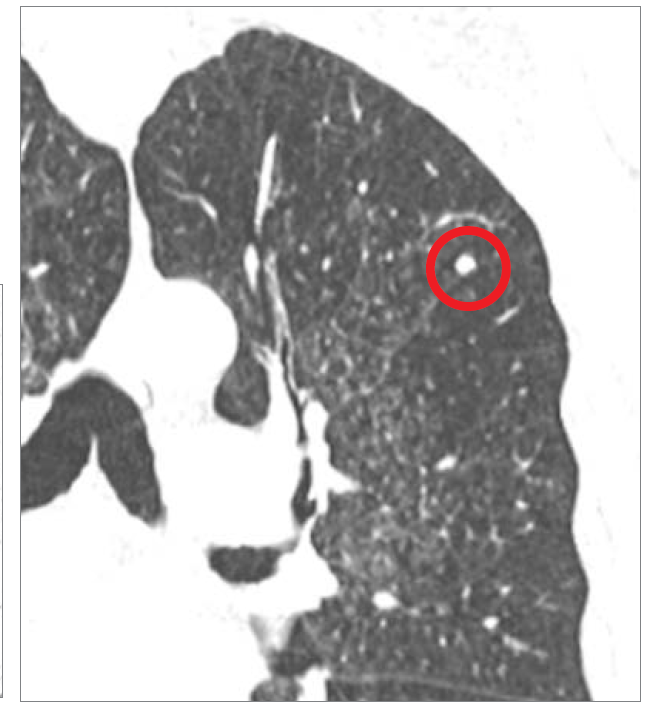

What is the red arrows?

PE